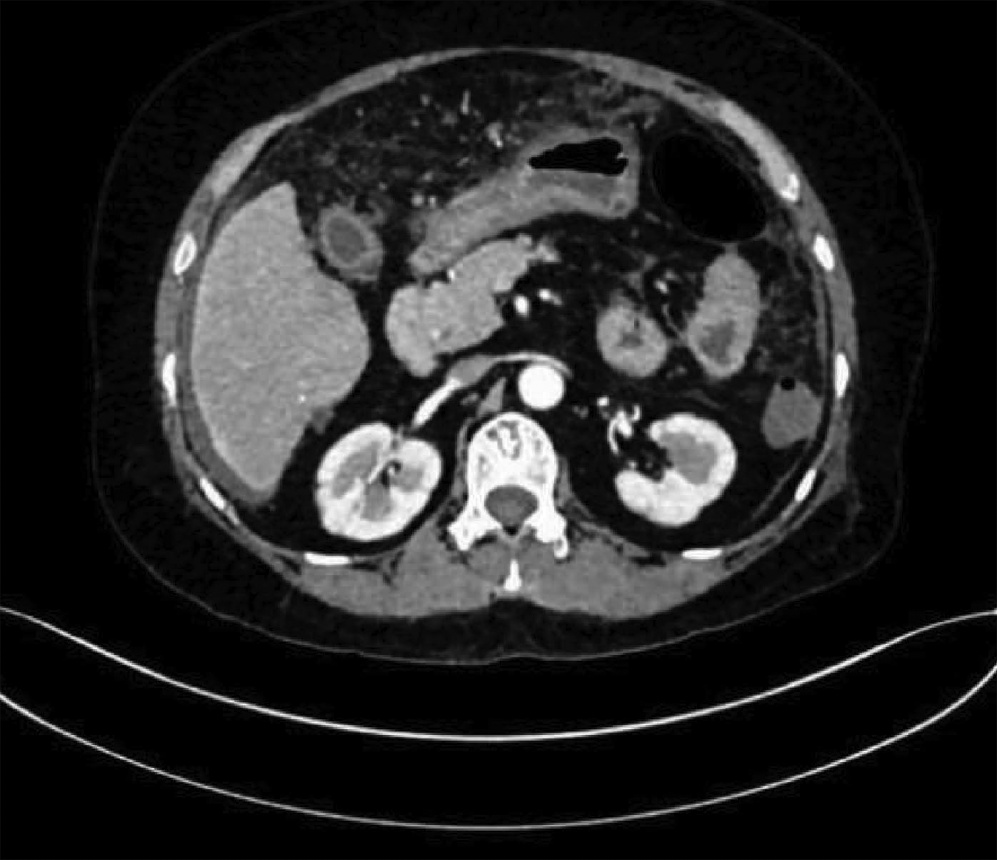

Spontaneous rupture of biliary dilatation with cancer: A case report

2022, 38(5): 1129-1130. DOI: 10.3969/j.issn.1001-5256.2022.05.031

Abstract: